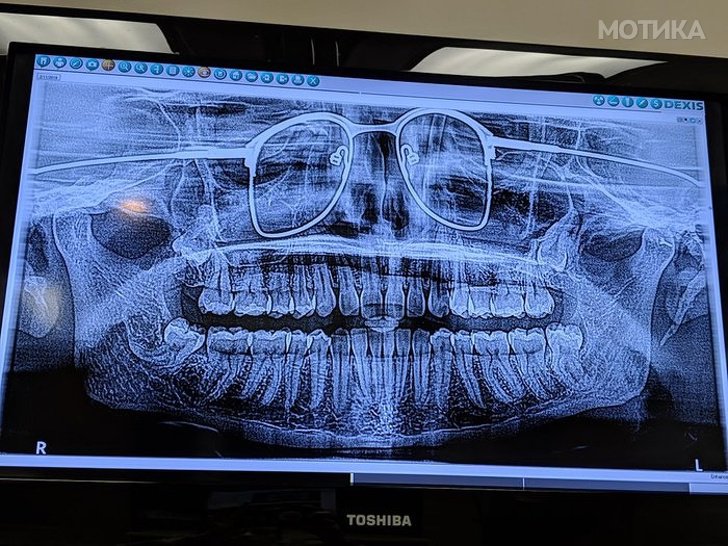

2. Панорамска снимка на вилицата. Човекот заборавил да ги отстрани очилата